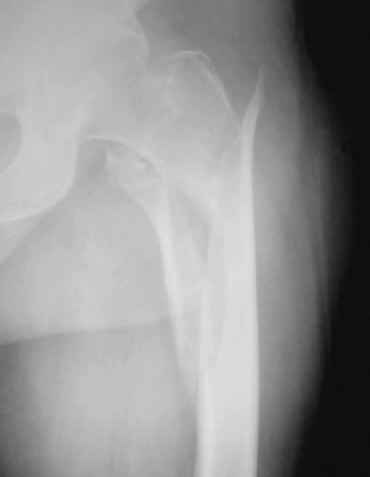

Пациент 83 года. Реконструктивный бедренный стержень Chm

коллеги в наличии есть только проксималный гвоздь chm длинна 260мм.отправить мы ее тоже никуда не можем т.к в облати внедряется тока у нас

Короткая версия 240 мм. Длинные начинаются с 260 мм? Попробуйте имеющуюся железку приложить к рентгенограмме - скорее всего, 260 мм будет маловато. Должна быть возможность связаться с поставщиком и поменять имеющийся гвоздь на аналогичный нужного размера.

День добрый! 240 мм однозначно короток, нужен миниум 300 мм, а то благие начинания заведут вас в ад осложнений. С диабетом на операции открывть ничего не нужно, только закрытая репозиция на ортопедическом столе под контролем ЭОПа. Без 100% анатомичной репозиции. Восстановить ось и ШДУ.